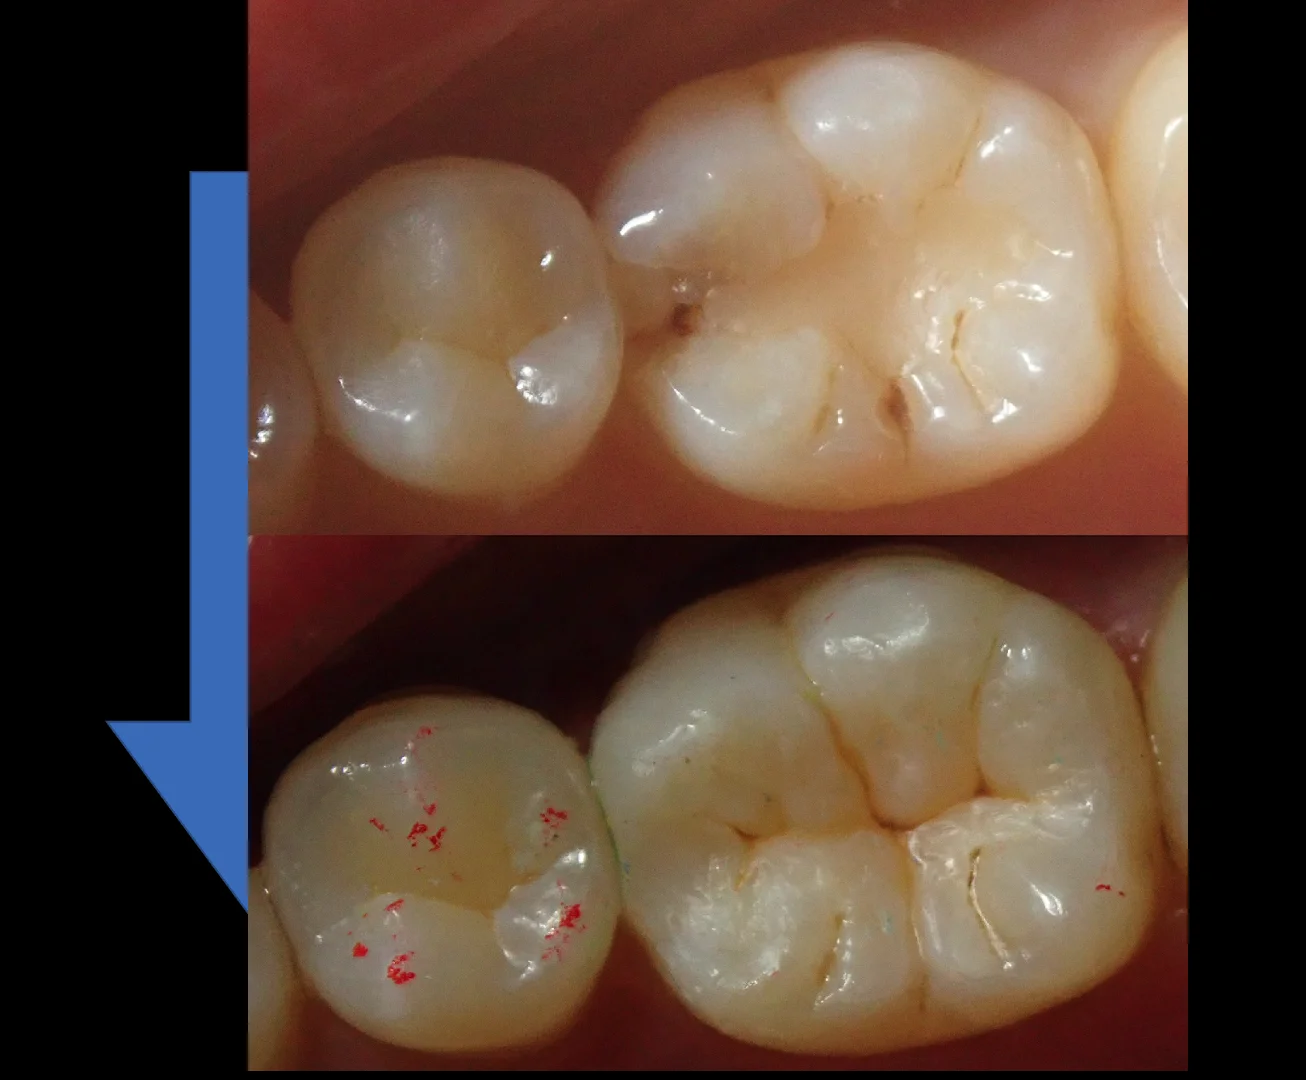

3人目はこちらの、竜ヶ崎市にて開業されている歯科医師の方です。

こちらが処置当日の写真ですね。

少し前すぎてカメラがあまりいいものではないため、画質が荒いです(⌒-⌒; )

その3年半後の写真がこちらになります。

著変なく状態は安定しているのがわかるかと思います。

この方は歯との間にも詰めているのですが、歯茎の状態も非常に良好なのがわかるかと思います。

レジンは汚れがつきにくいという特性があるのですが、結局それは材料や研磨のレベルで改善できる部分になりますので、そういう点でも術者の依存度合いが高い治療になりますね。